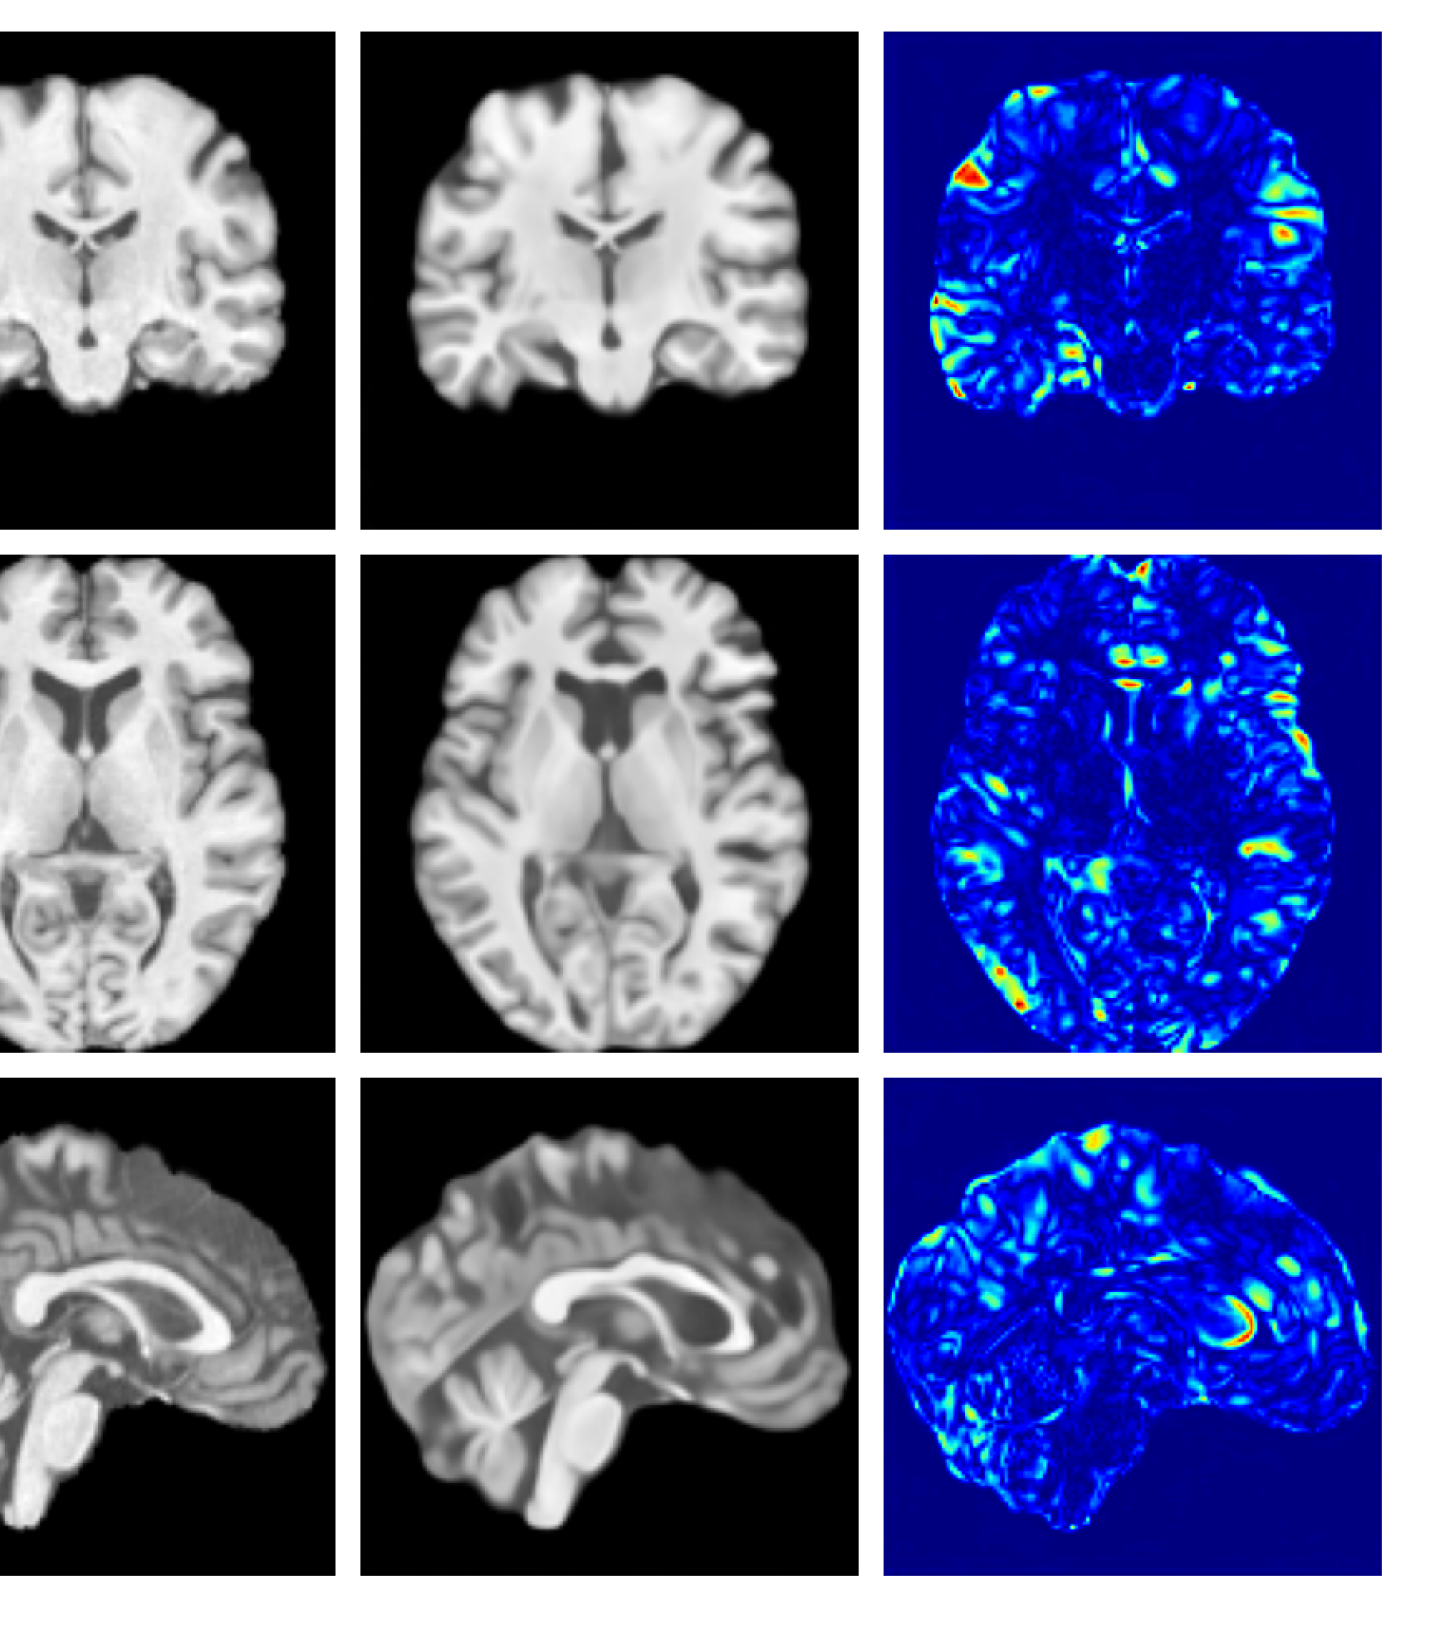

Figure 7 provides example reconstructions and anomaly maps for a healthy subject from the UK Biobank holdout test cohort.

Refer to caption

Figure 7: Example healthy reconstructions and anomaly maps for a sample from the UK Biobank healthy test cohort. For a healthy subject, we should observe no regions highlighted in the anomaly map.